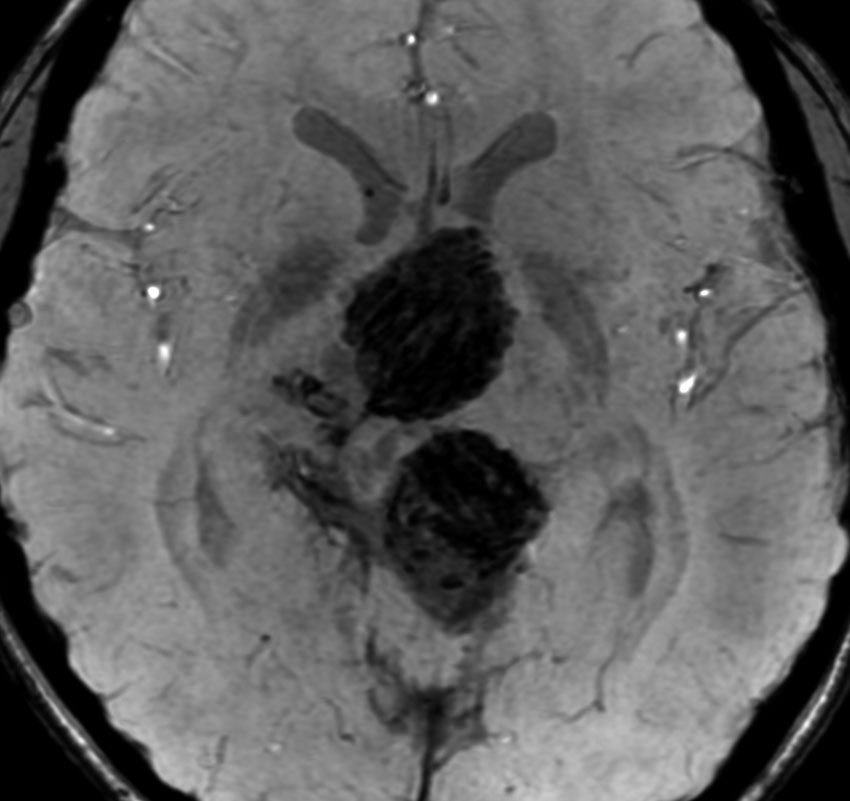

9歳男児の松果体奇形腫です。生検術と第3脳室開窓術を受けましたが,摘出術のリスクが高すぎるということで化学療法を6コース。2年間経過観察されましたが,腫瘍が増大しました。私のところへ来た時には,前後径73mmありました。

左からT2, swan, T1です。これが 類皮のう胞 dermoid cyst ということがわかります。類皮のう胞単独,あるいは成熟奇形腫の大部分としての類表皮のう胞は,かなり頻度の高いものです。松果体腫瘍で奇形腫を疑ったらまず,類皮のう胞の混在を疑います。それがあれば,かなりの確率で成熟奇形腫 mature teratomaです。

類皮のう胞は内部がほとんど皮脂,ケラチン,汗,毛髪なので,簡単に砕けるし,掻き出し吸い取ることができます。松果体成熟奇形腫の中では最も戦いやすい相手と言えるでしょう。再発しないようにするには,周囲ののう胞壁(真の腫瘍細胞)を完全摘出するしかありません。放射線も化学療法も何も効かないし,のこせば必ず再発します。

右迂回槽にちょっとdebrisは残っていますが完全摘出できました。病理は他の成分を少し混じる成熟奇形腫です。術後3年間再発はありませんし,学校へ通って体育もできています。

この手術はもちろん簡単ではありません,でもほとんどが類皮のう胞であるということがわかったので踏み込めたのです。